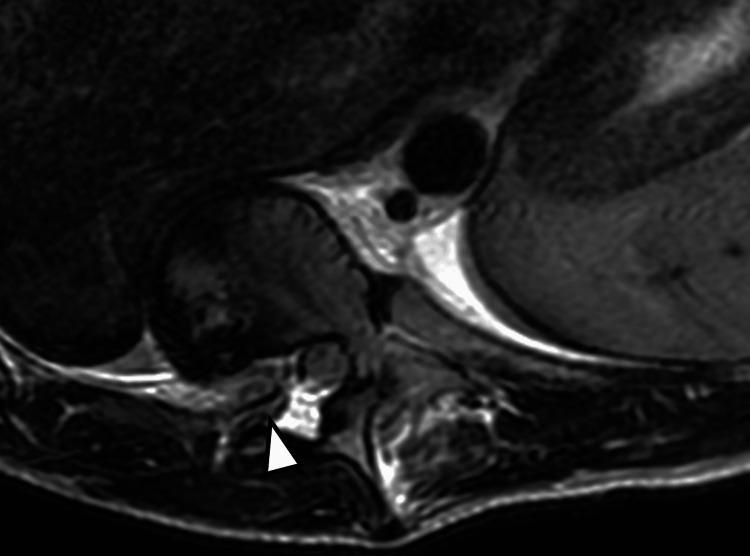

Neurofibromatosis type 1 (NF1) is frequently associated with a multitude of skeletal abnormalities including dystrophic scoliosis. A rare but severe complication of dystrophic scoliosis in NF1 is the herniation of rib heads into the spinal canal, potentially leading to devastating spinal cord compression. We present two pediatric cases of NF1-associated dystrophic scoliosis with intra-spinal herniation of rib heads. Case 1 involves a teenage male with progressive thoracolumbar scoliosis and protrusion of T10 and T11 rib heads into the spinal canal, who underwent successful posterior spinal fusion (T3-L3) with instrumentation, osteotomies, and rib head resection. Case 2 involves a teenage female with progressive thoracolumbar scoliosis and intra-spinal protrusion of T4 and T5 rib heads, who remains neurologically intact despite worsening curvature. Intra-spinal herniation of rib heads is a clinically important complication of NF1-associated dystrophic scoliosis requiring close surveillance. Familiarity with this complication is important as imaging findings may be subtle early on. Surgical management typically involves both spinal fusion and resection of rib heads to prevent neurological compromise, though timing may vary based on symptoms and progression. Multidisciplinary care is essential.

1型神经纤维瘤病(NF1)常伴有多种骨骼异常,包括营养不良性脊柱侧凸。NF1中营养不良性脊柱侧凸的一种罕见但严重的并发症是肋骨小头疝入椎管,可能导致毁灭性的脊髓压迫。我们报告两例NF1相关的营养不良性脊柱侧凸伴肋骨小头椎管内疝的儿科病例。病例1为一名青少年男性,患有进行性胸腰椎脊柱侧凸,T10和T11肋骨小头突入椎管,接受了成功的后路脊柱融合术(T3-L3),包括器械固定、截骨术和肋骨小头切除术。病例2为一名青少年女性,患有进行性胸腰椎脊柱侧凸,T4和T5肋骨小头椎管内突出,尽管脊柱侧凸加重,但神经功能仍保持完好。肋骨小头椎管内疝是NF1相关的营养不良性脊柱侧凸的一种重要临床并发症,需要密切监测。熟悉这种并发症很重要,因为早期影像学表现可能很细微。手术治疗通常包括脊柱融合和肋骨小头切除,以防止神经功能受损,不过手术时机可能因症状和病情进展而异。多学科护理至关重要。